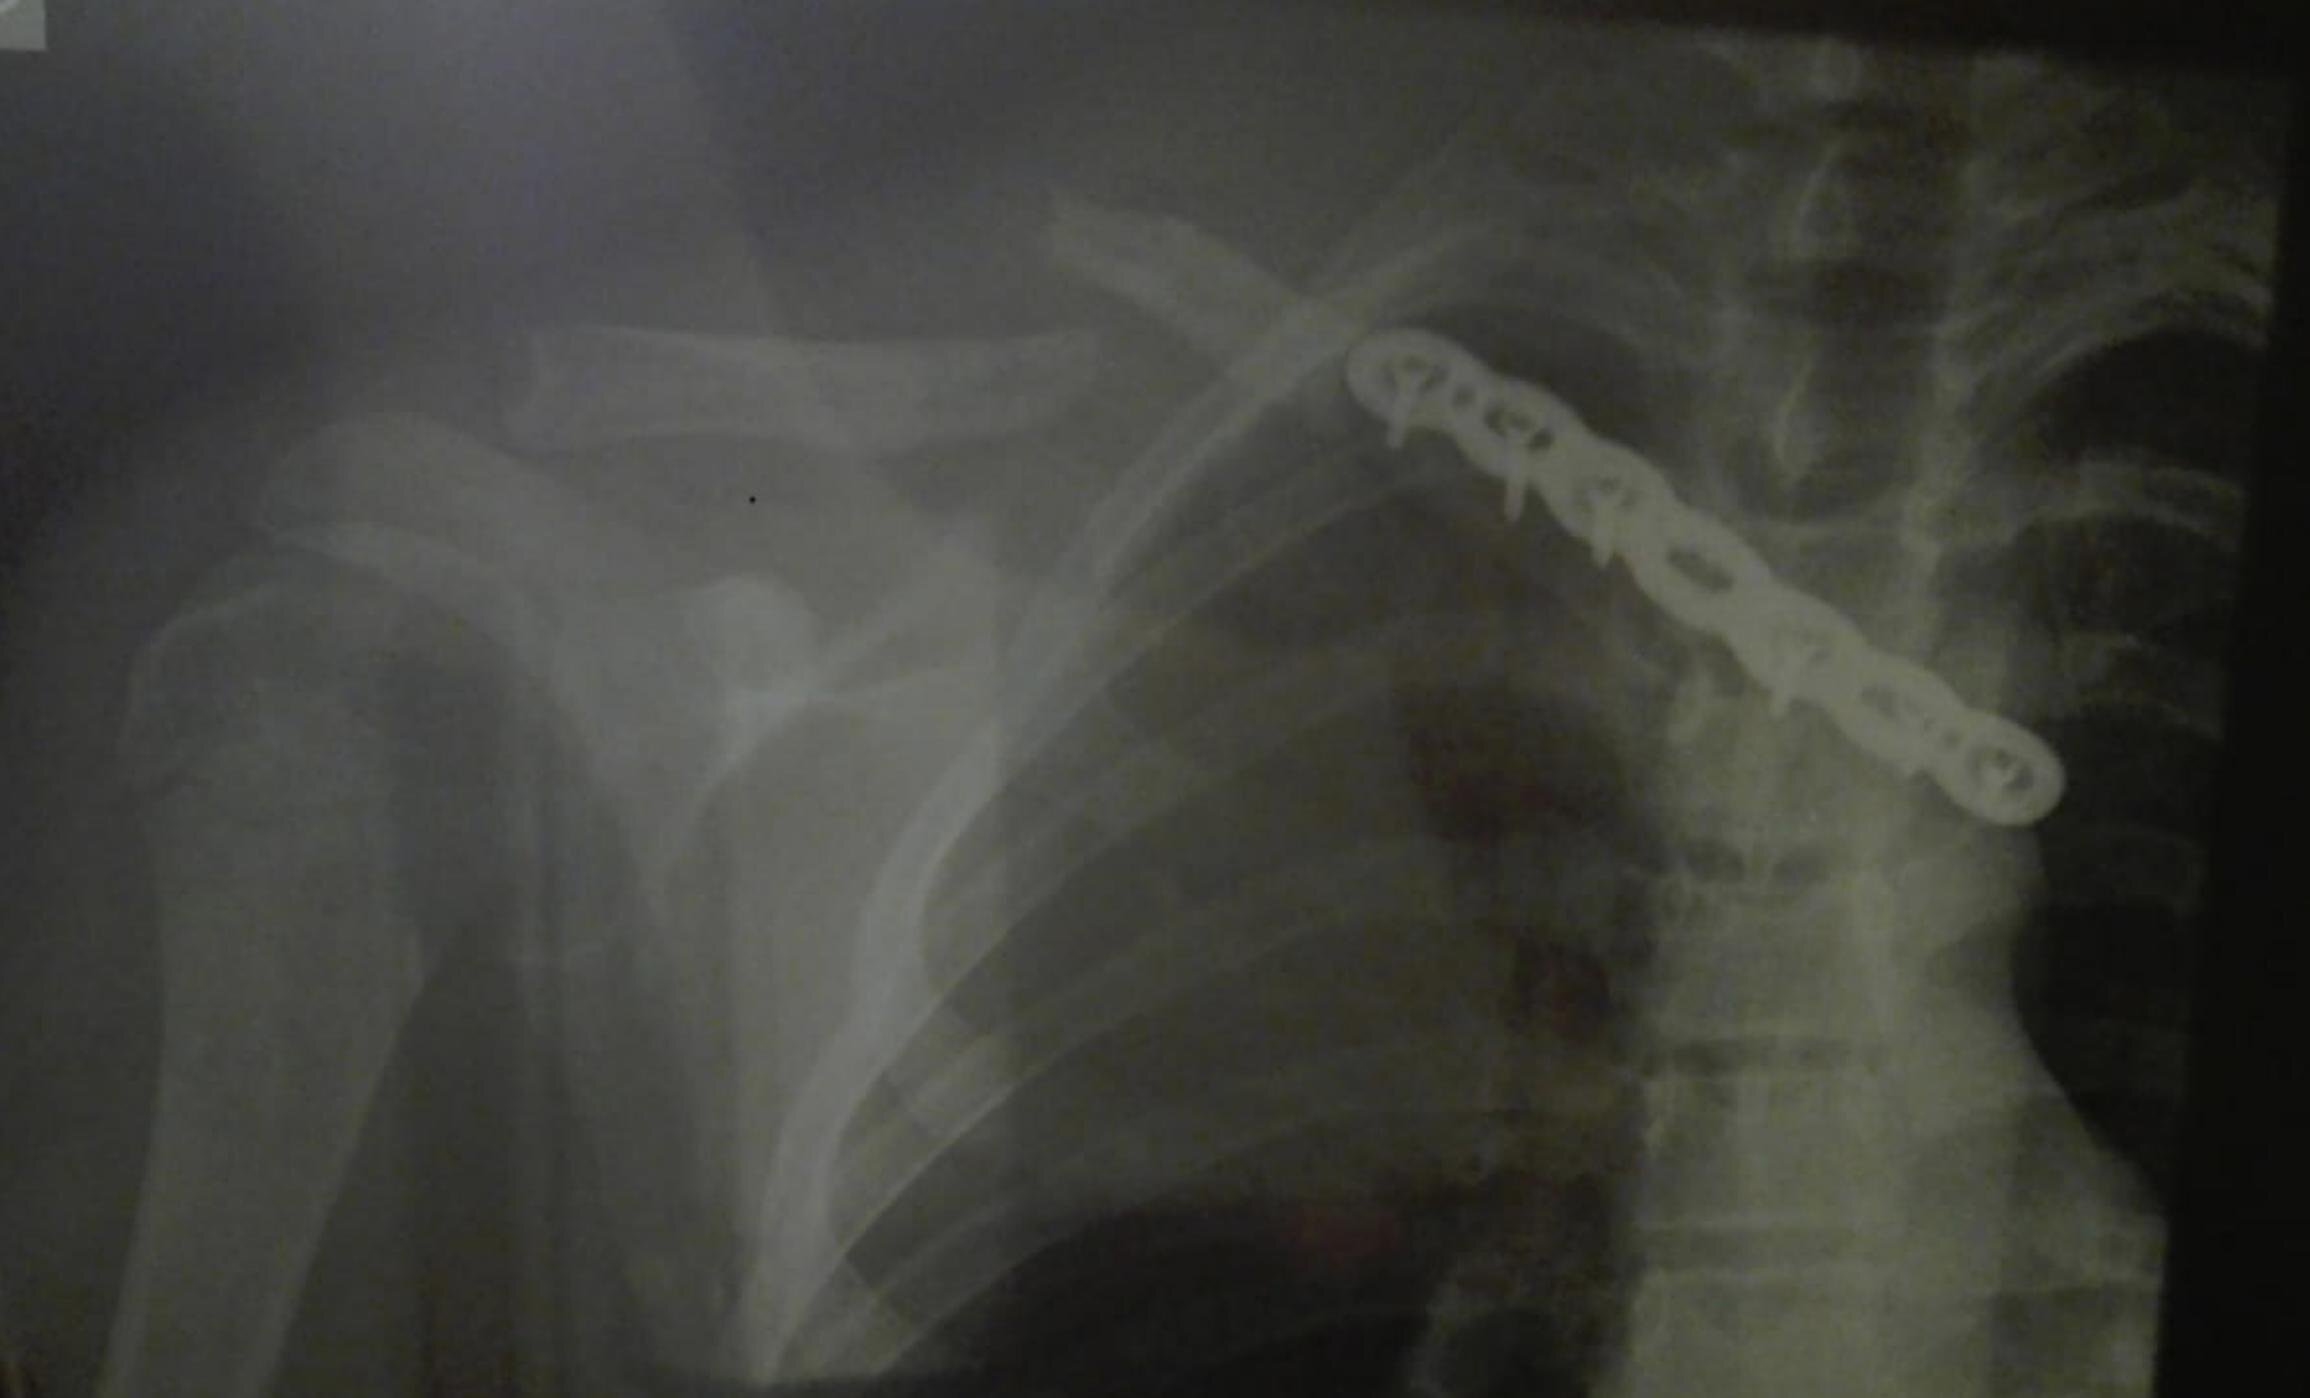

Uno de los ejemplos de operación publicados por Peláez en su cuenta de Twitter: